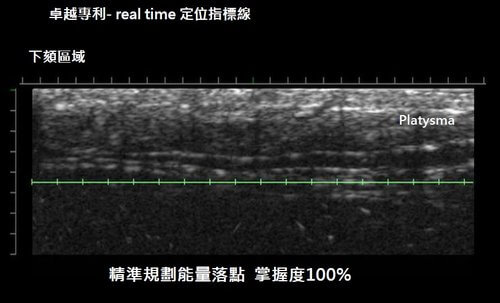

第三,即時(real-time)定位: 利用超音波隨時可成像的原理,在治療過程中同時提供即時影像定位,可以幫助治療者做更精準的治療(如圖四所示)

圖四, ulthera獨家的Deep See技術可以提供即時影像,讓操作的醫師更能準確掌握能量落點